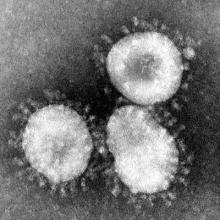

The rapid spread of the coronavirus (SARS-CoV-2) and the disease it causes (COVID-19) impacts all of us in many ways. This disease not only affects us physically, but also mentally and emotionally. For cancer patients, this pandemic adds to already existing stress and may worsen ongoing health… more

Given the rapid rise of COVID-19 cases around the world, scientists and clinicians are looking into the possible effects of common medications on COVID-19 progression and outcomes. Two medications commonly found on cancer patients' medication lists include non-steroidal anti-inflammatory drugs (… more

The coronavirus (SARS-CoV-2) that causes COVID-19 (the disease) is more dangerous to people with other health conditions, including cancer.

Please visit the National Cancer Institute's information page for people with cancer.